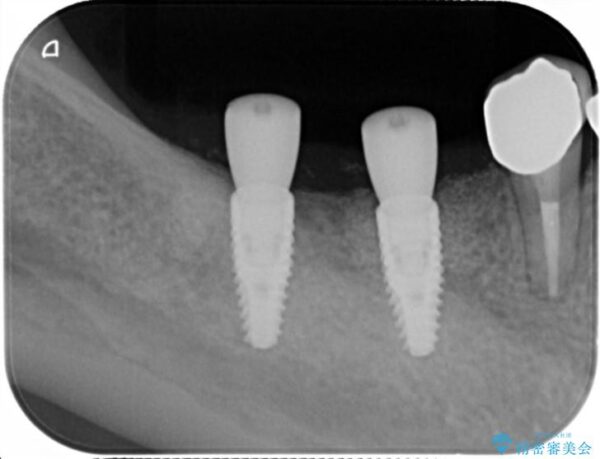

X線写真検査より、クラウンや銀歯の下で歯に大きな虫歯が発生し、抜歯を余儀なくされる状況でした。

虫歯に伴い歯槽骨の吸収も見られたので造骨後、インプラントを用いて咬合機能を回復します。